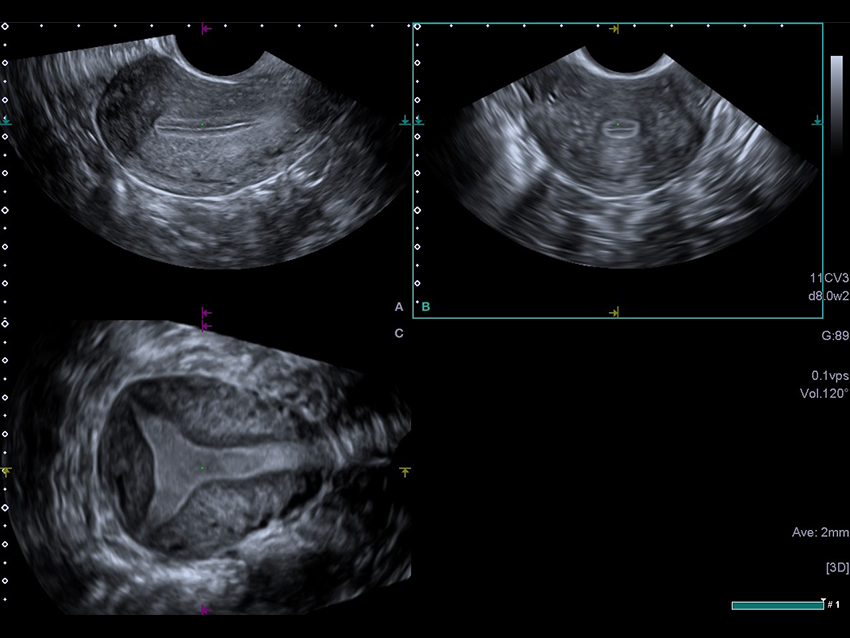

3D MPR зображення матки в трьох площинах з високою роздільною здатністю дозволяє клініцистам оцінити порожнину матки.